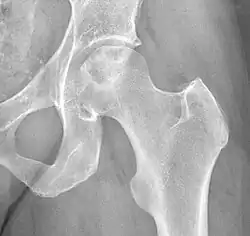

Chandler's disease, also known as idiopathic avascular osteonecrosis of the femoral head (ANFH or ONFH), is a rare condition in which the bone cells in the head of the femur (FH) die due to lack of blood. This disease is caused when blood flow is reduced to the part of a bone near a joint. It is specifically unique because the femoral head is for some reason the only affected part of the body and rarely travels down to the main part of the femur. In 1948, F. A. Chandler did a multi-case review and first released his interpretations as Coronary Disease of the Hip. This term is now considered incorrect as it improperly describes the actual disease.[1]

The current etiology or origin of this disease is unknown. Some studies theorized that bone remodeling is maintained in a microenvironment in the FH meaning that there is a greater local component to changes to the femoral head than the normal systemic way that bone remodeling is handled throughout the body. As a whole our body goes through bone remodeling using various hormones and glucocorticoids to balance the uptake and output of bone throughout the entire body. The local portion is considered to be controlled partially by inflammatory cells called cytokines and individual growth factors. The theory is that the local bone remodeling is malfunctioning and overpowering the systemic bone remodeling causing the FH to be highly susceptible to necrosis. Studies have determined that there are risk factors that are more than likely associated with the development of the disease but many of them are very broad and include large groups of people for example alcoholics, diabetics, and many other common core morbidities. Unfortunately, most are classified under idiopathic due to being unable to truly narrow down the origin of why it only happens to the head of the femur. What most clinicians observe is that the head of the femur seems to almost have a system of its own somewhat separate from the rest of the femur. There are many theories as to how the head of the femur dies unlike why it is happening.[3]